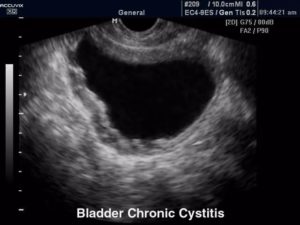

Воспаленные стенки обычно утолщены, а сам пузырь при остром заболевании увеличивается в размерах, а при хроническом может уменьшаться.

Что выявляют на УЗИ при цистите

К общим изменениям относят:

- Утолщение стенки мочевика в области воспаления.

- Асимметрию мочевого пузыря. Воспаленная часть будет больше, чем здоровая.

- Отечность устья мочеиспускательного канала.

При некоторых формах цистита исследования будут иметь специфические проявления.

Так, для герпетического и язвенного цистита характерным изменением будет наличие эрозий и язвенных образований на внутренней поверхности мочевика.